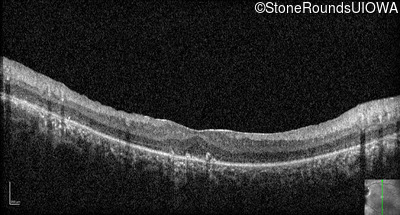

Age at visit: 15 years

This 15 year old male has had very poor vision and nystagmus since the first year of life.